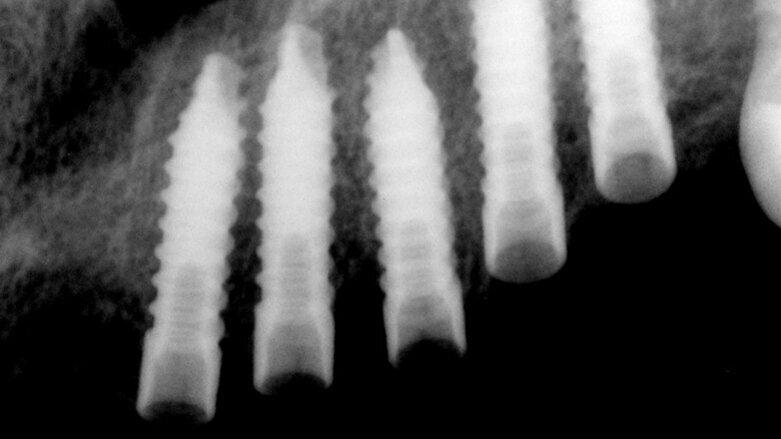

UIS IMPLADENTA obsahuje kompletní nabídku jednofázových a dvoufázových implantátů. Mini samořezné (MS), bikortikální samořezné (BS)

– jednofázové implantáty. V nabídce současně dvoufázové úzké válcové (NS) a cylindrické samořezné implantáty (CS) včetně abutmentů. Celistvost a kompletnost zajištuje speciální nabídka čepelkových – plátkových implantátů řada PROFI+.

Univerzální Implantátový Systém po své 30leté výrobní tradici nabízí stomatologům jak jednofázové, tak i dvoufázové implantáty, které jsou vhodné

k řešení různých, někdy i komplikovaných stavů po ztrátách zubů.

Implantáty UIS IMPLADENTA jsou vyráběny z certifikovaného biokompatibilního materiálu 99,6% Titanu Gr. 4. Na dentální trh se dodávají v praxi vyzkoušených požadovaných rozměrech včetně individuálních rozměrů mimo standardní nabídku na vyžádání.

Ke speciálnímu typu implantátů UIS IMPLADENTA se řadí samořezné bikortikální implantáty (BS) – jednofázové implantáty určené k okamžitému zatížení. Jsou vhodné zejména do bradové oblasti dolní čelisti. Méně vhodné do oblasti horních čelistí. Zavádět lze jak do vhojené alveolární kosti, tak i okamžitě po extrakcích frontálních zubů, pokud je dostatečně široký a vysoký kostní alveol nebo tělo dolní čelisti. V současnosti

se vyrábějí v nejčastějších délkách 12/14/16/18/20 a 22 mm, z čehož orální část má výšku 5,5 mm. Průměr implantátu je 3,5 mm.

Zavádění bikortikálních implantátů je jednoduché. Pilotním vrtákem o požadovaném průměru se provede kostní preparace pomalými otáčkami, a to tak, abychom se dotkli kraniální plochy dolní kompakty mandibuly. Tato preparační fáze je důležitá proto, že tento implantát se musí částečně vnořit do této vrstvy.

Po této preparaci se vybraný implantát vloží do kostního kanálku a pomocí ručního nástroje – zavaděče nebo ráčny se pomalu zavádí do kostní tkáně. Předem se dá použít i závitník k vytvarování kostního lože.

Po správné preparaci je implantát velmi pevně zakotven a pokud je to nutné lze jej pomocí ohybače přihnout k dosažení paralelity.

Pro stabilitu bikortikálních implantátů je nutná výška kostní tkáně kolem 13 mm při 6mm výšce orální části k protetické sanaci.

Bikortikální implantát (BS) je možné zatížit po 1 až 3 týdnech, ojediněle lze tyto implantáty zatížit ihned po provedené operaci. Možnost zatížení závisí na kvalitě a kvantitě kostní tkáně a na jejich lokalizaci. Nejvhodnější indikací použití bikortikálních implantátů (BS) je dokonalá retence hybridních zubních náhrad dolní čelisti. Dají se použít i jako dočasné implantáty, vmezeřené implantáty nebo jako náhrady při ztrátě jednoho zubu apod. Pro zkušeného implantologa je zavádění těchto implantátů bez rizika.